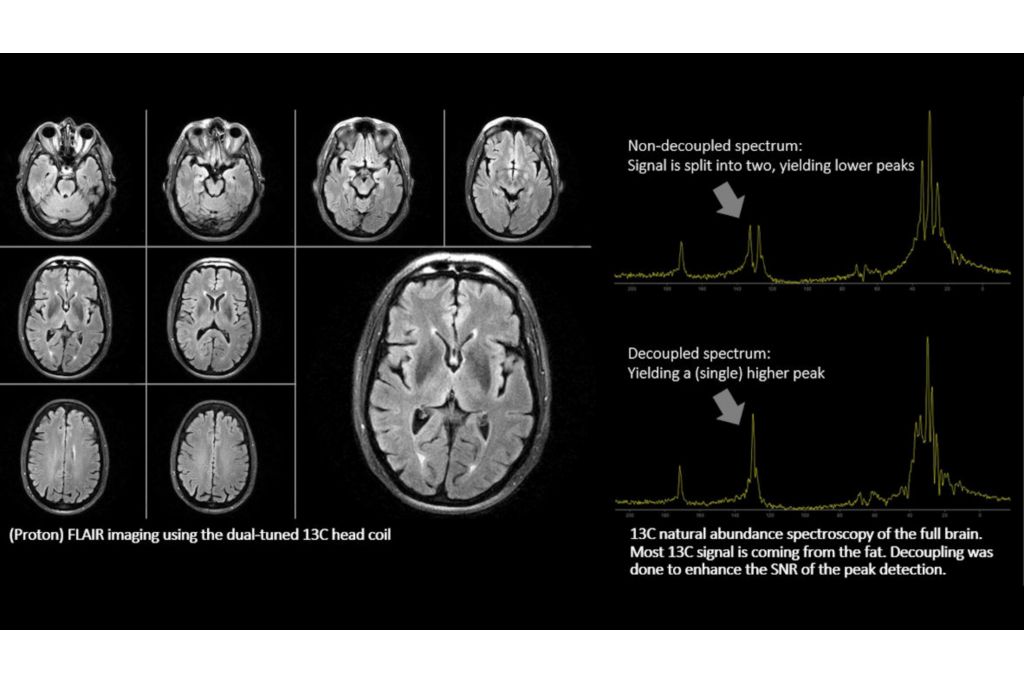

The dual tuned head coil from RAPID Biomedical allow you to perform brain exams, including acquisition of proton and other nuclei (31P, 13C, 23Na), without switching coils, in routine scan times. A full brain study, including both proton (1H) and sodium (23Na) imaging can be completed in 30 minutes, all organized in one ExamCard, using the same dual tuned head coil. A Sodium (23Na) brain scan can be completed in less than 15 minutes.

Combined with our multi-nuclei specialist package, the dual tuned head coil allows to explore new imaging pathways by integrating multi-nuclei studies in your day-to-day workflow.